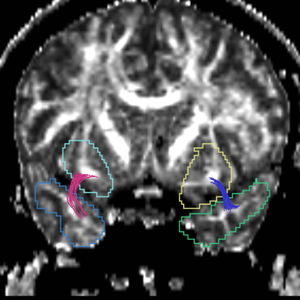

Uncinate Fasciculus

Internal Capsule

Fornix

Cingulum

Arcuate Fasciculus